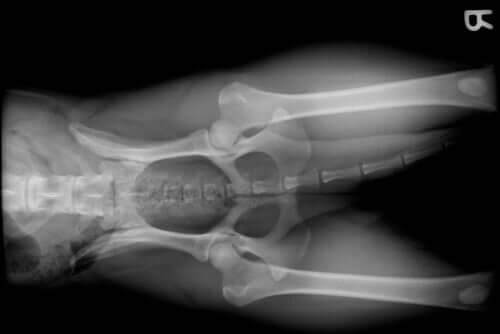

Einer der vielen Gründe, warum ein Hund regelmäßig durch den Tierarzt untersucht werden muss, ist das Erscheinen von Gelenkkrankheiten. Ein Spezialist kann dieses Problem bei den Tieren früh feststellen, indem er auf Lahmen und machmal auch akuten Schmerz achtet.

- Die Rasse. Bestimmte Hunderassen, wie etwa der deutsche Schäferhund, entwickeln oft Hüftdysplasie. Im Unterschied dazu leiden andere große Rassen, wie beispielsweise der Golden Retriever, der Rottweiler oder der Dobermann oft aufgrund ihrer Größe und ihres schnellen Wachstums unter Schulter- oder Ellenbogendysplasie.

- Fortgeschrittenes Alter. Genau wie auch bei anderen Säugetieren und dem Menschen treten bei Hunden altersspezifische Krankheiten auf. Hier spricht man von degenerativer Gelenkerkrankung bei Hunden.

- Wachstumsprobleme. Das Wachstum ist bei Hunden, sowie auch bei anderen Spezies, ein schwieriger Moment. Ernährungsmangel, Hormonprobleme oder die Rasse können Probleme in den Gelenken hervorrufen.

- Brüche, bei denen ein Gelenk betroffen ist.

- Riss des vorderen Kreuzbandes. Aufgrund von Überbelastung, zu viel Fitness oder der Zugehörigkeit einer kleinen Rasse kann das vordere Kreuzband reißen. Das bringt ernsthafte Probleme für die Gelenkgesundheit bei Hunden mit sich.